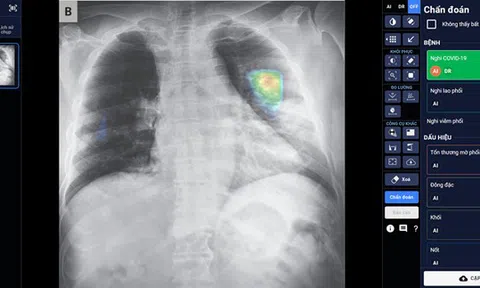

Sản phẩm Trợ lý Bác sĩ cho Chẩn đoán hình ảnh - “DrAid for Radiology” của Công ty VinBrain (tập đoàn Vingroup) đã giành được Giải thưởng Công nghiệp ACM SIGAI 2021 cho sản phẩm ứng dụng trí tuệ nhân tạo (AI) xuất sắc nhất.

Dự án "Trợ lý bác sỹ" - bài toán đó chưa ai trên thế giới giải được. 4,7 tỷ người trên thế giới chưa có bác sỹ khám chữa bệnh, hiện 10% người bệnh chết vì chuẩn đoán sai. Đó là cơ hội mà mình nhìn thấy, tại sao mình dám giải một bài toán như vậy?